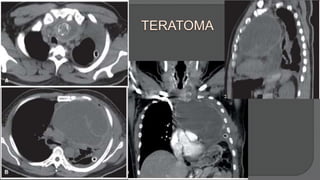

Benign teratomas. Most common germ cell tumor in the mediastinum, (60%-70%) of all mediastinal

tumors.

Characterized: mature tissues derived from all three germinal layers.

Histologically: cartilage, bone, fat, hair, and squamous and glandular epithelia

CT scan: a multilocular but well-circumscribed cystic anterior mediastinal mass containing fluid and

fatt density.

Tumor markers: AFP, β-hCG usually normal

Benign teratomas are not responsive to radiation therapy or chemotherapy

Typical CT findings + normal serum tumor marker levels  complete surgical excision without

biopsy